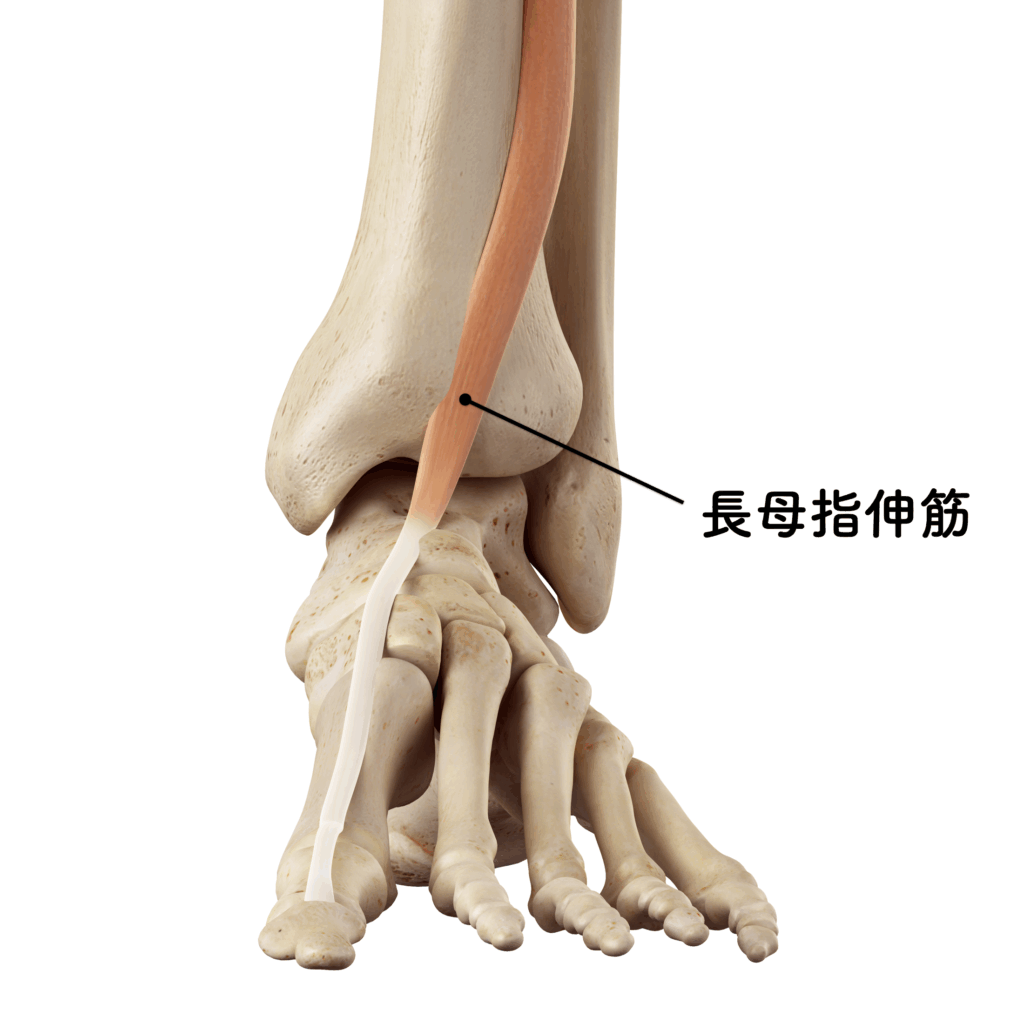

原因③ 筋肉バランスの崩れ——「伸びる筋」と「縮む筋」

足の小指は、小趾外転筋・短小趾屈筋・虫様筋・骨間筋など、非常に繊細な筋バランスによって支えられています。これらの筋のうち一つでも弱化すれば、他の筋が代償的に過剰収縮し、結果として骨を引っ張る力の方向がズレていきます。

とくに現代人に多いのが、「足趾を伸ばす筋(=伸筋群)」の機能低下です。たとえば短趾伸筋や長趾伸筋の活動が低下すると、対抗する屈筋群(長趾屈筋・足底方形筋)が優位になり、筋力のアンバランスが生じます。さらに、このアンバランスが「滑走軌道の乱れ」として現れ、小趾のねじれや屈曲変形を招く温床となるのです。

私はこの状態を、「足の感覚が眠っている」と表現しています。

靴や靴下に守られた生活で、足指を“伸ばす・広げる”機会が激減し、感覚入力と出力(運動)のループが断たれているからです。

開帳足とは、単なる骨格の広がりではありません。

本来、足趾の動きを支える足底方形筋・虫様筋・骨間筋などの滑走ラインが乱れることで、筋肉が骨を正しく支えられなくなった結果として、アーチが崩れていくのです。

特に第4〜5中足骨の間隔(intermetatarsal angle)が拡がると、小趾を内側へ引き込むトルクが増し、外反母趾や内反小趾といった“対称的な趾変形”が時間をかけて進行していきます。

開帳足は、単なる骨格の広がりではなく、筋肉バランスの崩壊の結果です。足底方形筋や虫様筋の滑走軌道が乱れ、骨間筋が適切に働けなくなると、第4〜5中足骨の間隔が開き、外反母趾や内反小趾といった対称的な変形が起こります。